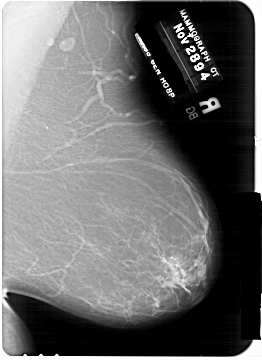

A_1769_1.RIGHT_CC

RIGHT_MLO LINES 6871 PIXELS_PER_LINE 4966 BITS_PER_PIXEL 12 RESOLUTION 43.5 NON_OVERLAY